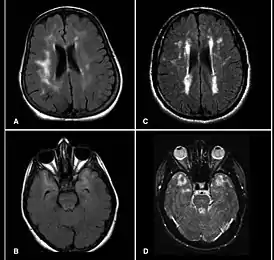

![]() МРТ головного мозга больного синдромом CADASIL | |